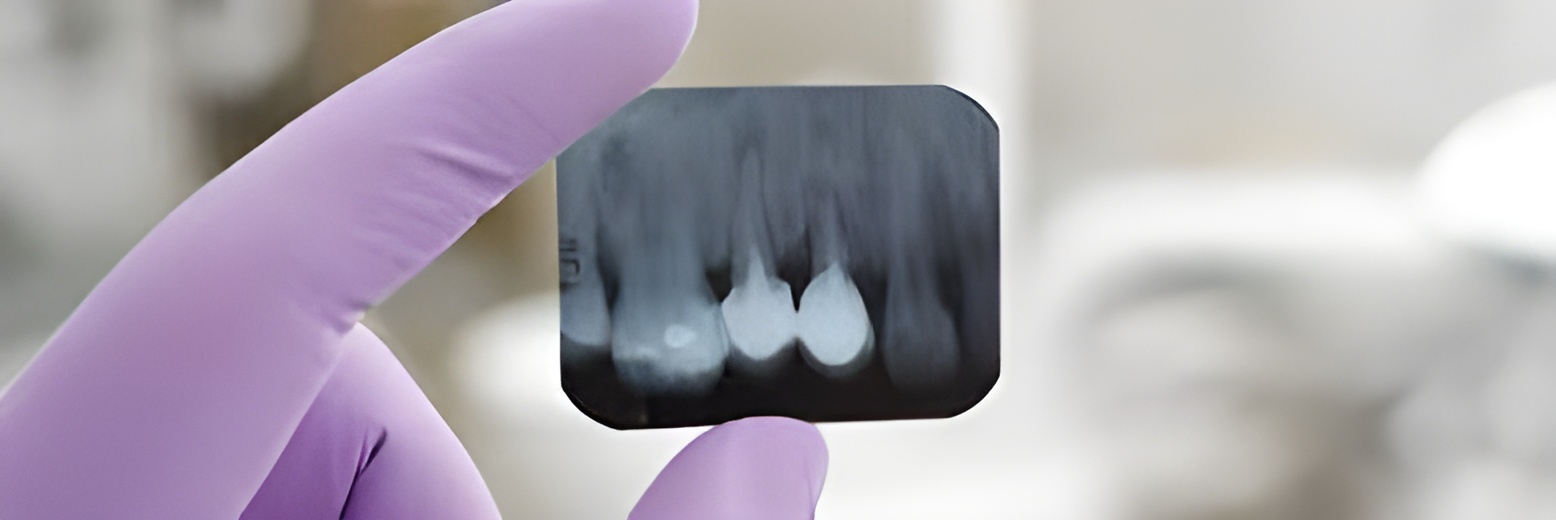

Imagerie en odontologie S3

6 examensExamens disponibles

Radio S3 #1

Radio S3 #2

Radio S3 #3

Radio S3 #4

Radio S3 #5

Radio S3 #7

Imagerie en odontologie S5

Radio S5 #1

Radio S5 #2

Radio S5 #3

Radio S5 #4

Radio S5 #5

Radio S5 #7

Imagerie en odontologie

5 examensExamens disponibles

Radio S6 #1

Radio S6 #2

Radio S6 #3

Radio S6 #4

Radio S6 #5